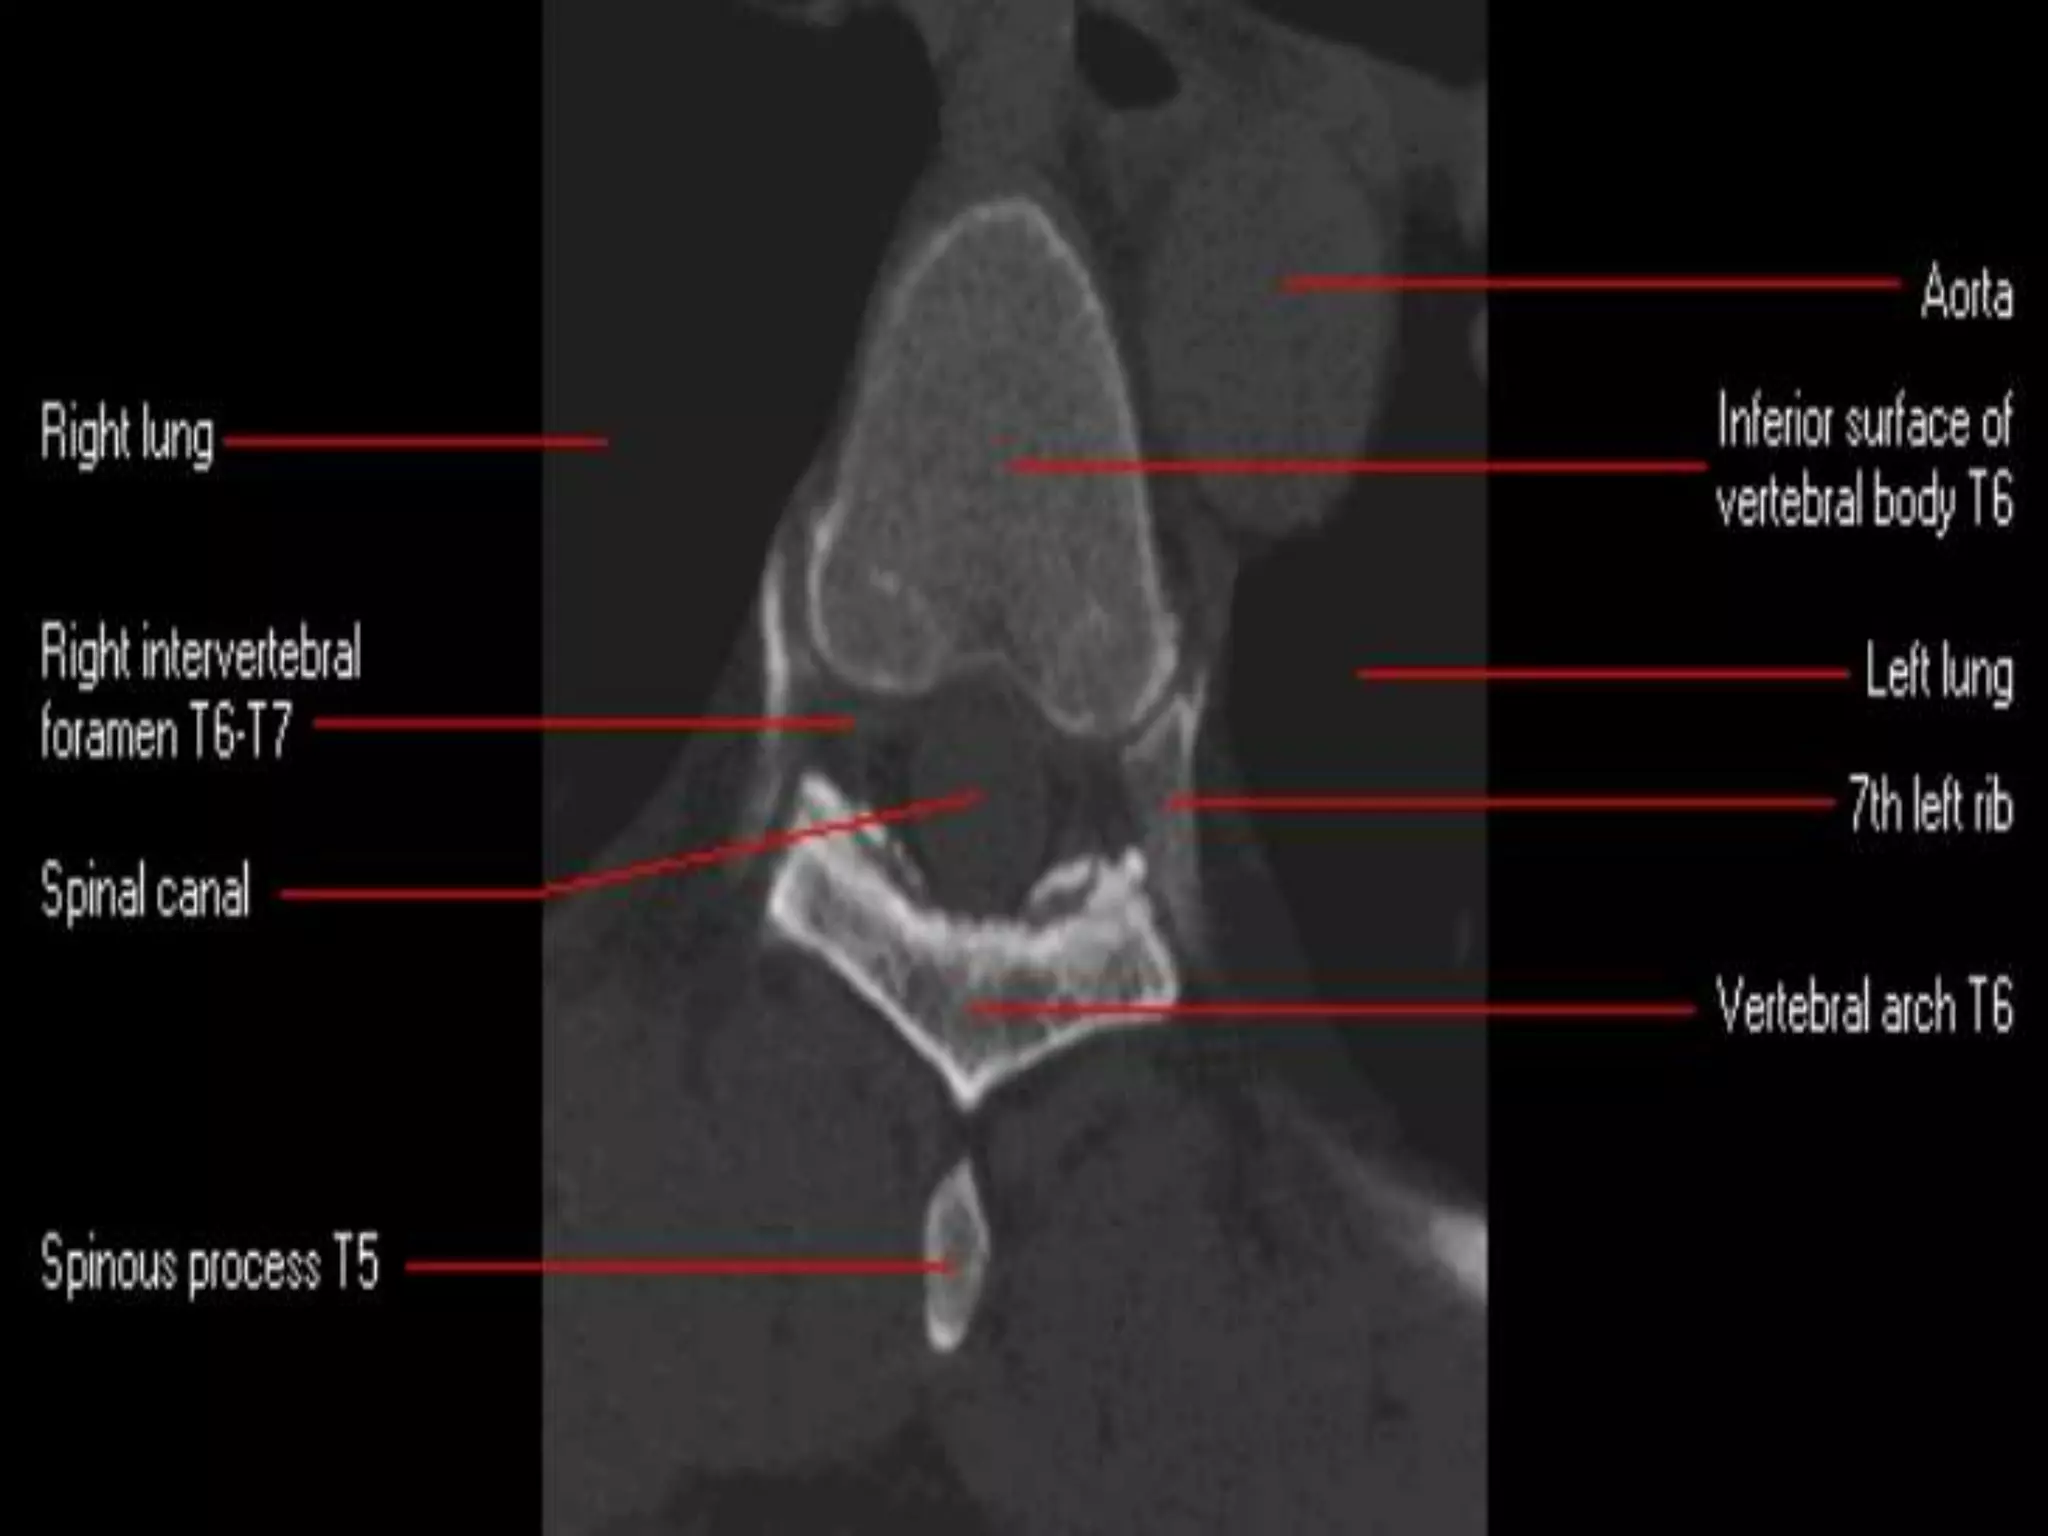

CT of the Thoracic Spine: Anatomy.

1-vertebral body, 2-neural foramen, 3-articular

pillar 4-lamina, 5-spinous process.

CT of theThoracic Spine: Anatomy.

1-vertebral body, 2-neuralforamen, 3-articular pillar 4-lamina, 5-spinous process.